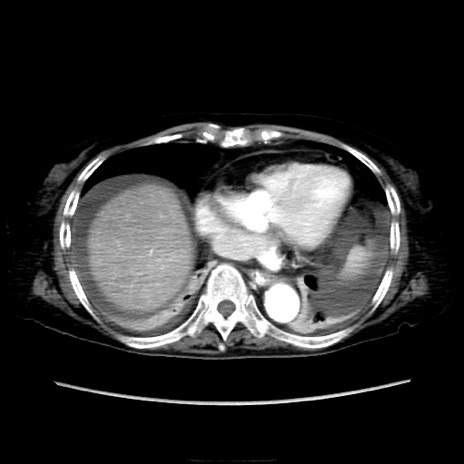

症例40(横断像)

【症例】90歳代女性

【主訴】腹痛・嘔吐

【現病歴】 食欲低下、嘔吐があり昨日他院受診。肺炎と診断され入院となる。入院後より腹部全体に圧痛あり。胃管留置され経過みていたが、症状持続するため、

当院転院となる。

【身体所見】腹部:中央に激痛あり、圧痛あり、反跳痛不明

【データ】WBC 17100、CRP 18.82

横断像